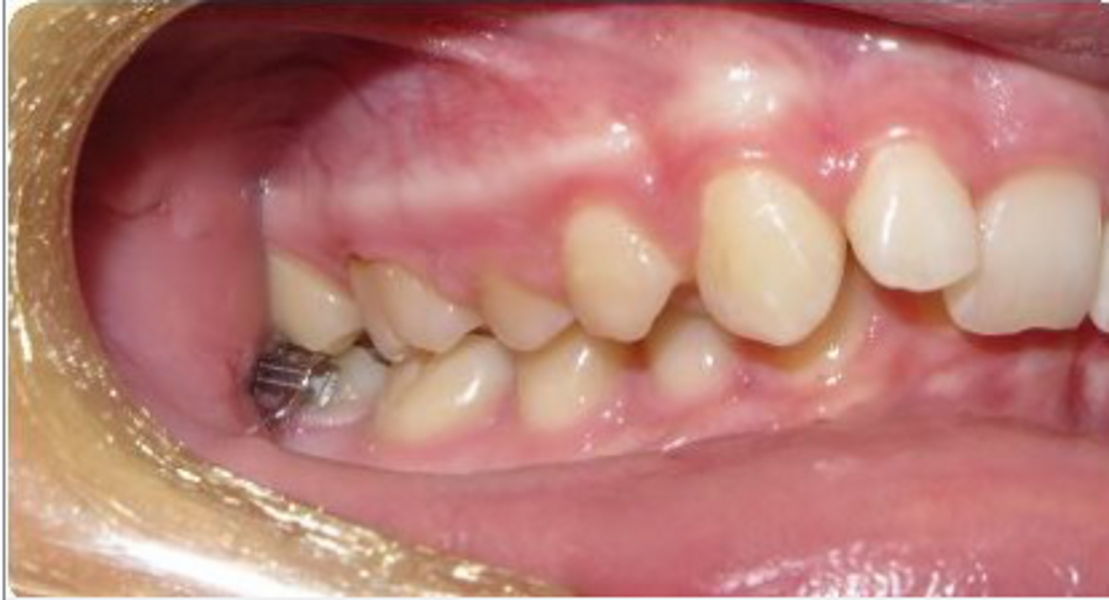

Fig. 18a: Class II malocclusion requiring fixed appliance treatment. (a) Lateral view. (b) Occlusal view.

Fig. 18b: Class II malocclusion requiring fixed appliance treatment. (a) Lateral view. (b) Occlusal view.

Fig. 19a: After six months of the Carriere Motion appliance and aligners. (a) Lateral view. (b) Occlusal view.

Fig. 19b: After six months of the Carriere Motion appliance and aligners. (a) Lateral view. (b) Occlusal view.